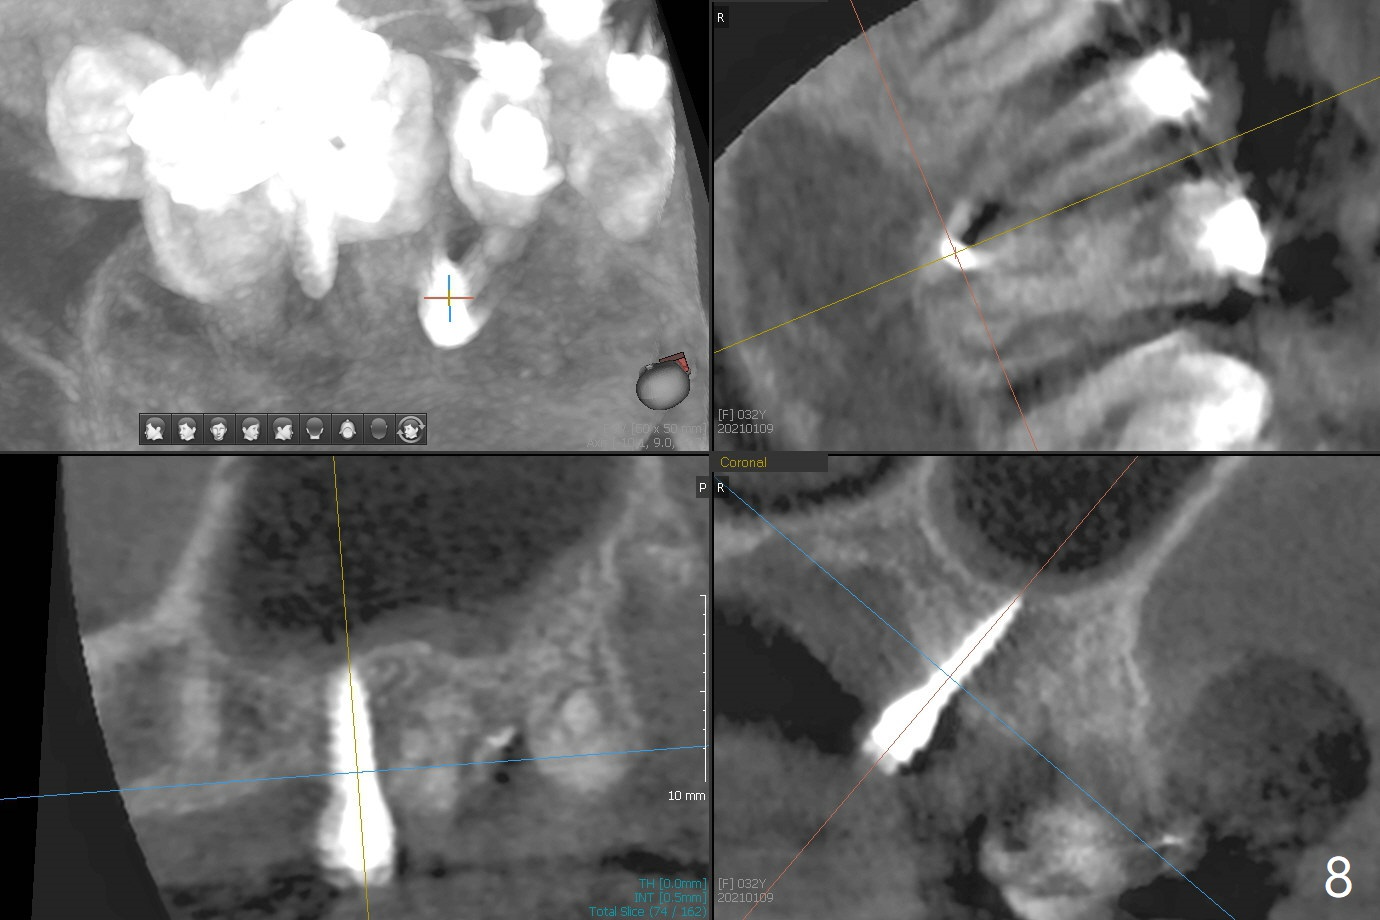

矫正器放置后一个月,正好有充裕时间,匆忙研究全景片(最好CT),好像左上6近中间隙大,近中颊侧,远中腭侧似乎是种植位点(图一:白圆圈),植入越高越宽,不容易伤及邻牙牙根。但是微型植体种植原则是必须种植在角化龈,减少炎症(以前不明白为什么)。当植体在移动牙龈植入时(图二:白箭头),牙龈浮起来,估计非角化牙龈也不能与植体产生紧密结合。取出后,完全可以在6近中颊侧角化龈植入,但是仔细检查发现远中颊侧角化龈更宽,所以在那里扎根(图二:黑箭头),因此腭侧就得选择近中(图三)。微型植体可以即刻使用,power chains常滑脱,压迫牙龈,在这个病例很可能进入远中牙间隙,所以需要在远中边缘嵴加树脂(图四,五:* (1.6x8mm))。第二天远中颊侧植体松动,取出后,插入2x10毫米一段式植体,仍然松动(图六)。CT显示植体下缘穿破牙槽骨(图七,骨质吸收严重与图八近中牙槽骨高度对比)。如果在近中颊侧重新植入微型植体,必须使用6毫米长植体(图九),所以最好在远中颊侧重新植入(图十:红色),缺损区(黑色)植骨。在使用14 niti时,左下7松动,病人同意拔除8,以后后推7,然后6种植(图十一:(左上8已拔除(x))),同时左上6远中植骨,左下8远中牙槽窝放置浸泡PRF液体胶原塞(图十二:1),近中牙槽窝粘性骨粉(2),最后牙槽窝上部PRF膜(3),PGA缝线。可能需要Cytoplast。